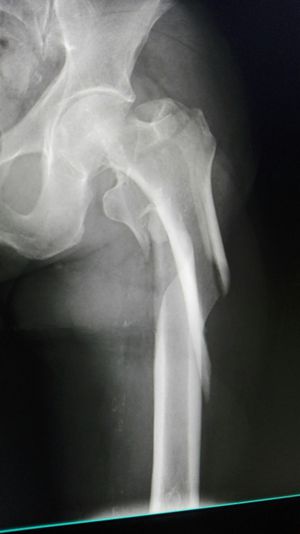

Xray

Fracture

Ouch